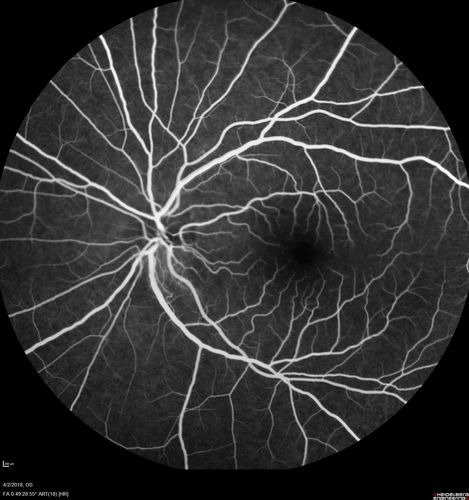

Cat Scratch - Neuroretinitis OD AND retinitis OS - Bartonella henselae positive

27 year old female with exposure to cats and prior fever.  Reports with recent vision loss right eye.  She was treated with doxycycline and within 2 weeks the right eye looks better.  Then she skipped all follow-up visits.  The right eye presented 20/200 and the left 20/16